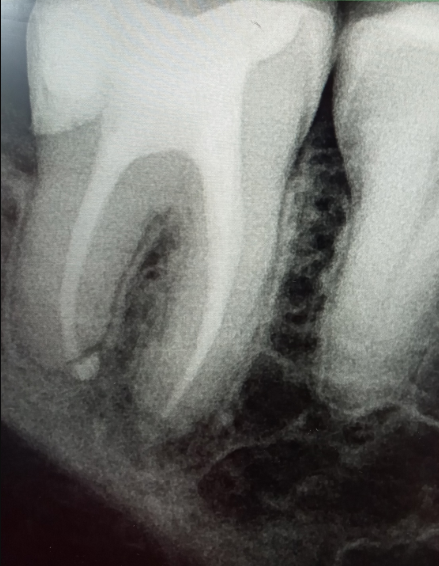

alewka213213 Опубликовано 10 декабря, 2024 Автор Поделиться Опубликовано 10 декабря, 2024 (изменено) В 08.12.2024 в 19:48, Carioznik сказал: Дело в инфекции, которая находится внутри зуба, а за пределами зуба -это её следствие. Нет зуба - нет инфекции. Это вариант удаления, он даёт 100% результат. Почистить каналы -тоже равно убрать инфекцию. Это вариант лечения, но даёт уже не 100 % результат. Хочется сохранить зуб (показаний к удалению, кстати, пока не видно) - перелечивайте. Не хотите лечить - удаляйте. Решать Вам. Cходил, чтобы перелечить, но решили не делать этого, так как врач заметил, что кажется воспаление уменьшается! И это при том что зуб без нерва, мы ничего не делали, а оно вон как... Или нам кажется? По крайне мере увеличения вроде нет. Вот, тоже выскажите мнение, пожалуйста. Пол года назад: Сейчас: Изменено 10 декабря, 2024 пользователем alewka213213 Ссылка на комментарий

Carioznik Опубликовано 10 декабря, 2024 Поделиться Опубликовано 10 декабря, 2024 (изменено) 57 минут назад, alewka213213 сказал: кажется воспаление уменьшается! Оченивать динамику нужно по КТ. По обычным снимкам всё может быть очень обманчиво. В зависимости от проекции (а её невозможно, при обычном снимке, сделать одинаковую)- будет разный размер. Вот вам пример: посмотрите на свою ладонь, а потом поверните ее ребром (сначала она была по площади - большая, а когда повернули - стала вдруг уже маленькая) Изменено 10 декабря, 2024 пользователем Carioznik 1 Ссылка на комментарий